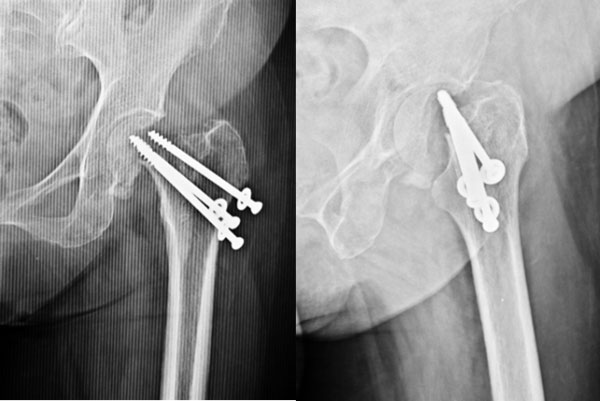

3 months post surgery

In her sleep one day she suddenly felt a sudden sharp pain in the hip joint, afterwards she was ok, so she continued to walk on the leg. She came back to us after a few days of limping and not being able to walk as earlier. The x-rays at that time showed this picture – where the screws had cut out of the ball (femoral head) and were even pinching on the socket. This was the cause of her pain, limp & shortening.